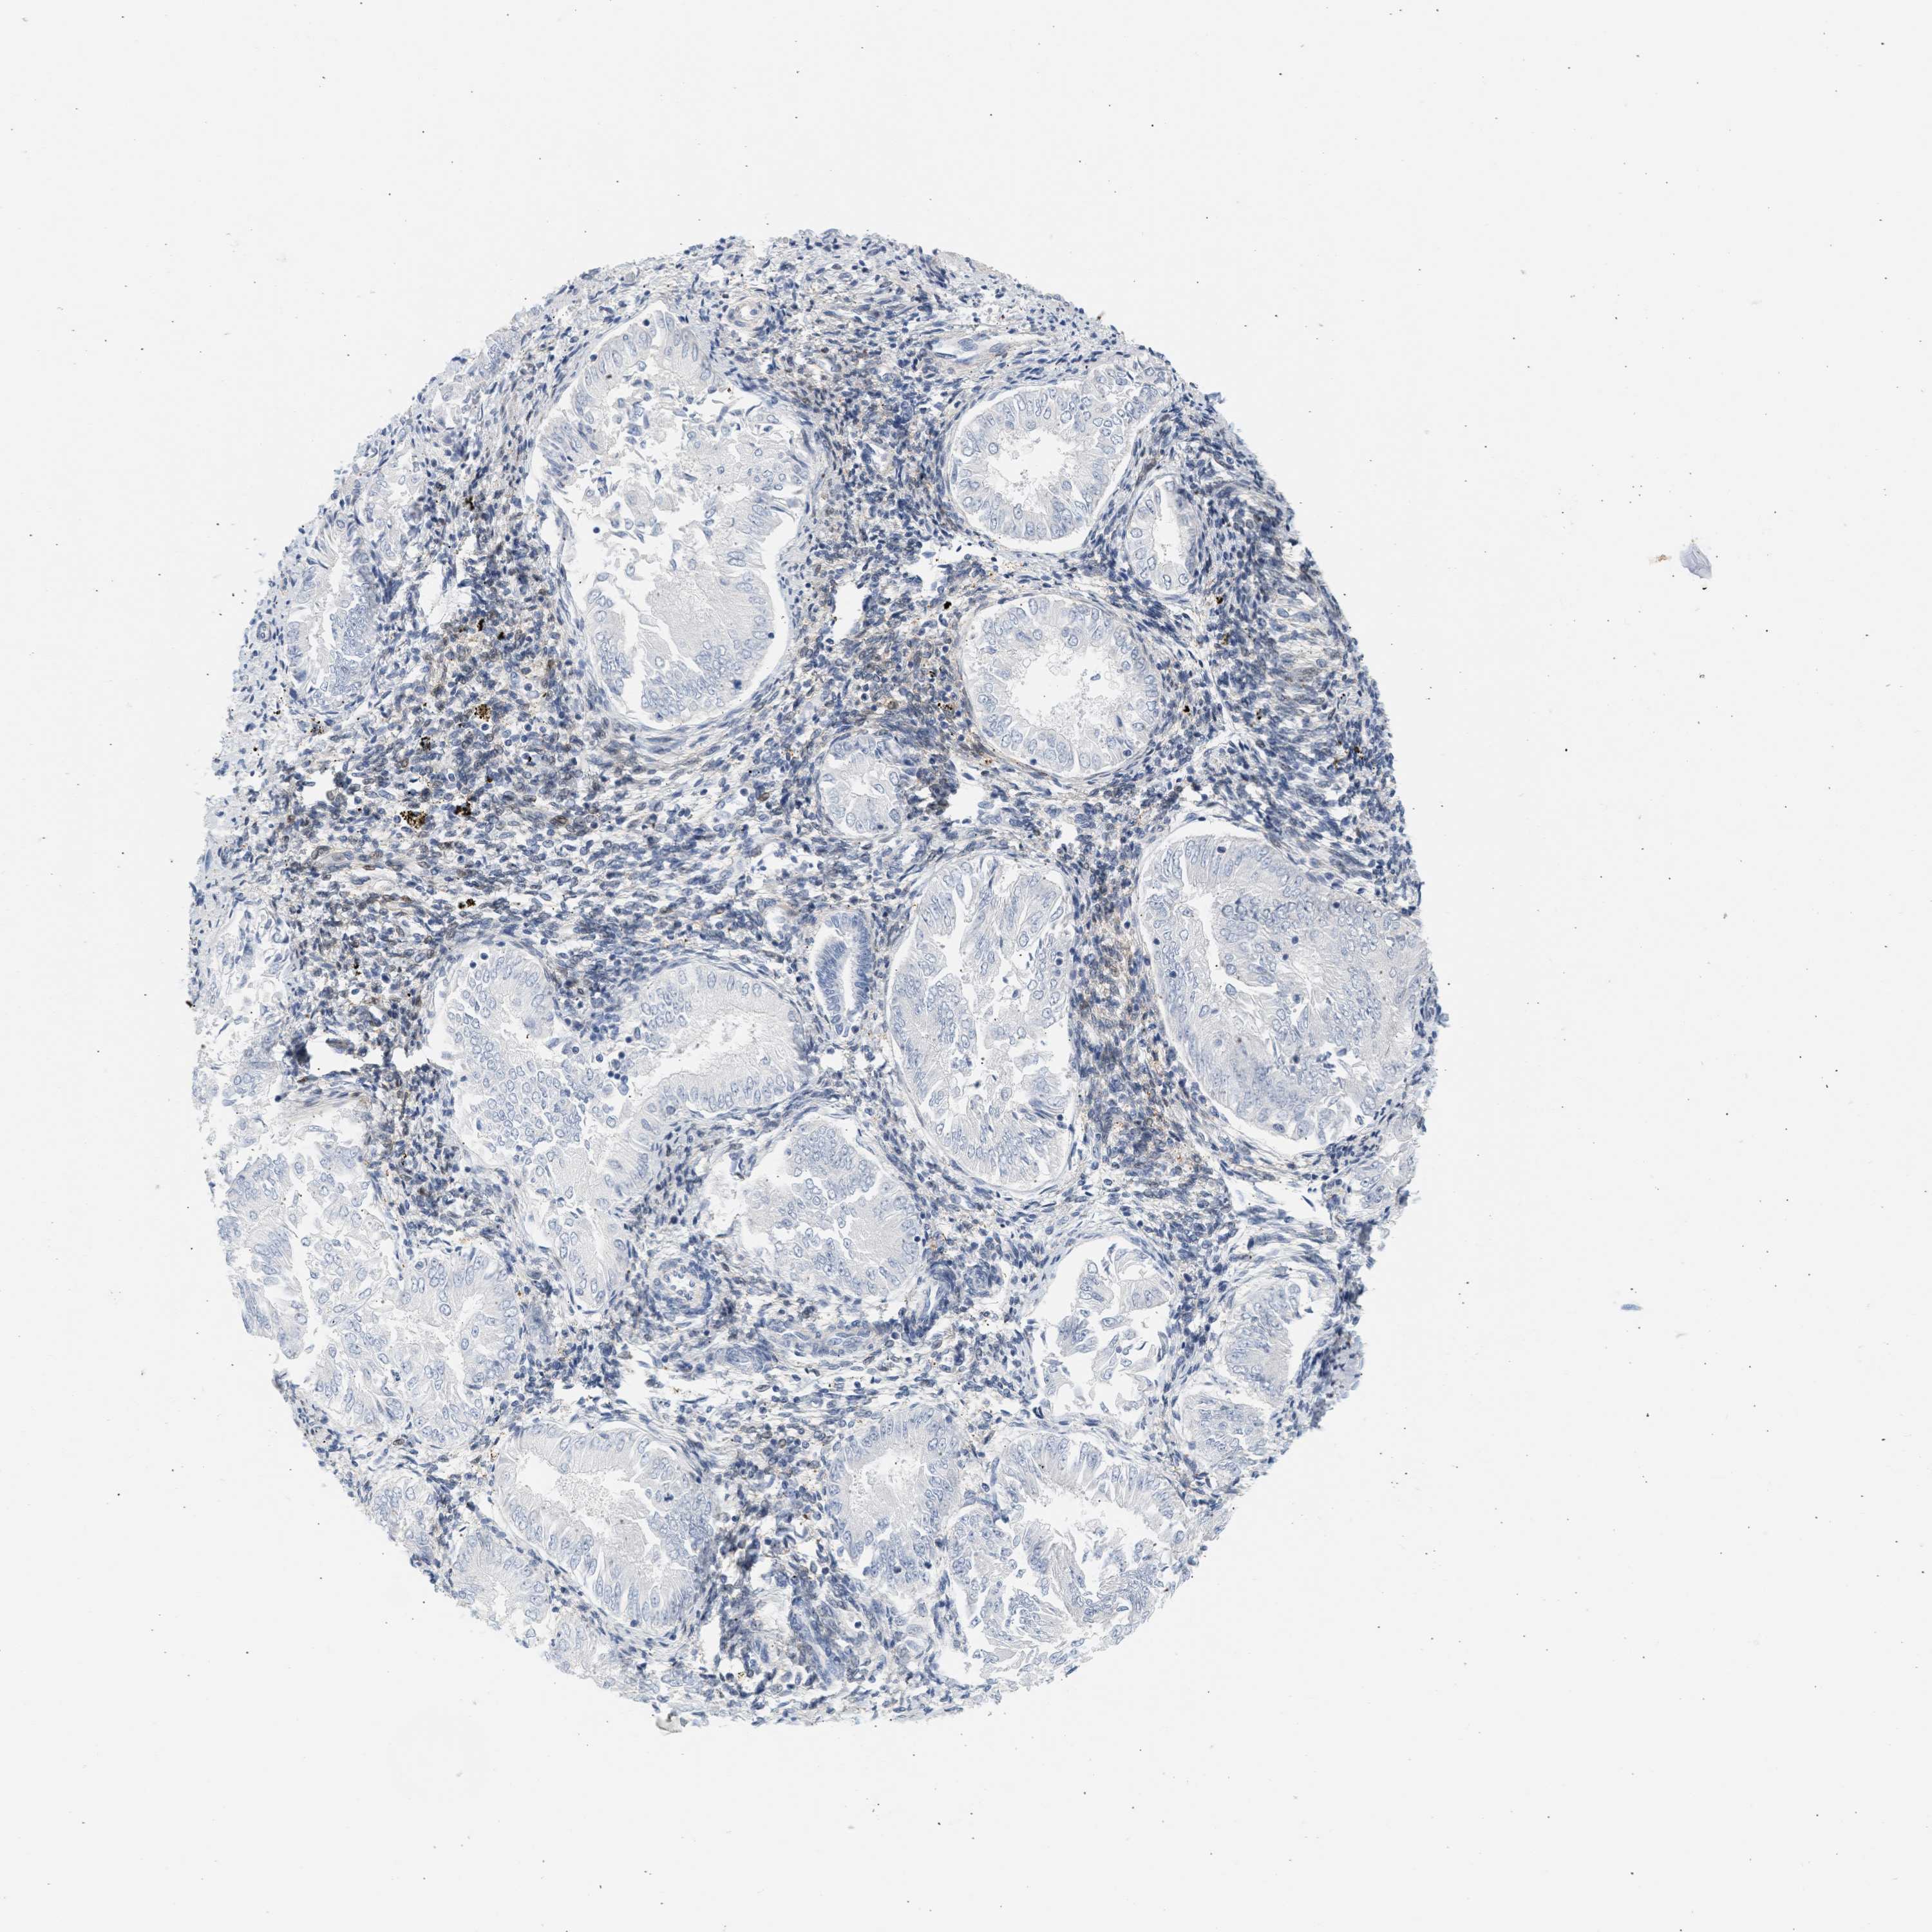

ENDOMETRIAL CANCER - Protein expressioni

A mouse-over function shows sample information and annotation data. Click on an image to view it in a full screen mode. Samples can be filtered based on level of antibody staining by selecting one or several of the following categories: high, medium, low and not detected. The assay and annotation is described here.

Note that samples used for immunohistochemistry by the Human Protein Atlas do not correspond to samples in the TCGA dataset.

Antibody stainingi

Antibody staining in the annotated cell types in the current human tissue is reported as not detected, low, medium, or high, based on conventional immunohistochemistry profiling in selected tissues. This score is based on the combination of the staining intensity and fraction of stained cells.

Each image is clickable and will lead to virtual microscopy that enables deeper exploration of all samples and also displays staining intensity scores, fraction scores and subcellular localization as well as patient and tissue information for each sample.

Antibody HPA018034

Staining

High

Medium

Low

Not detected

Intensity

Strong

Moderate

Weak

Negative

Quantity

>75%

75%-25%

<25%

None

Location

Nuclear

Cytoplasmic/membranous

Cytoplasmic/membranous,nuclear

Adenocarcinoma, NOS